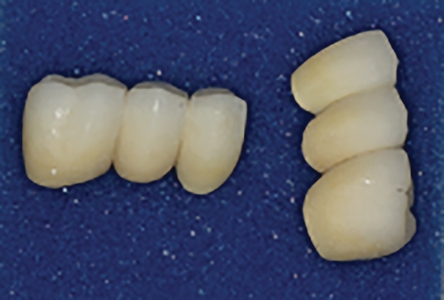

Bis-bake for try-in

Immediate insert